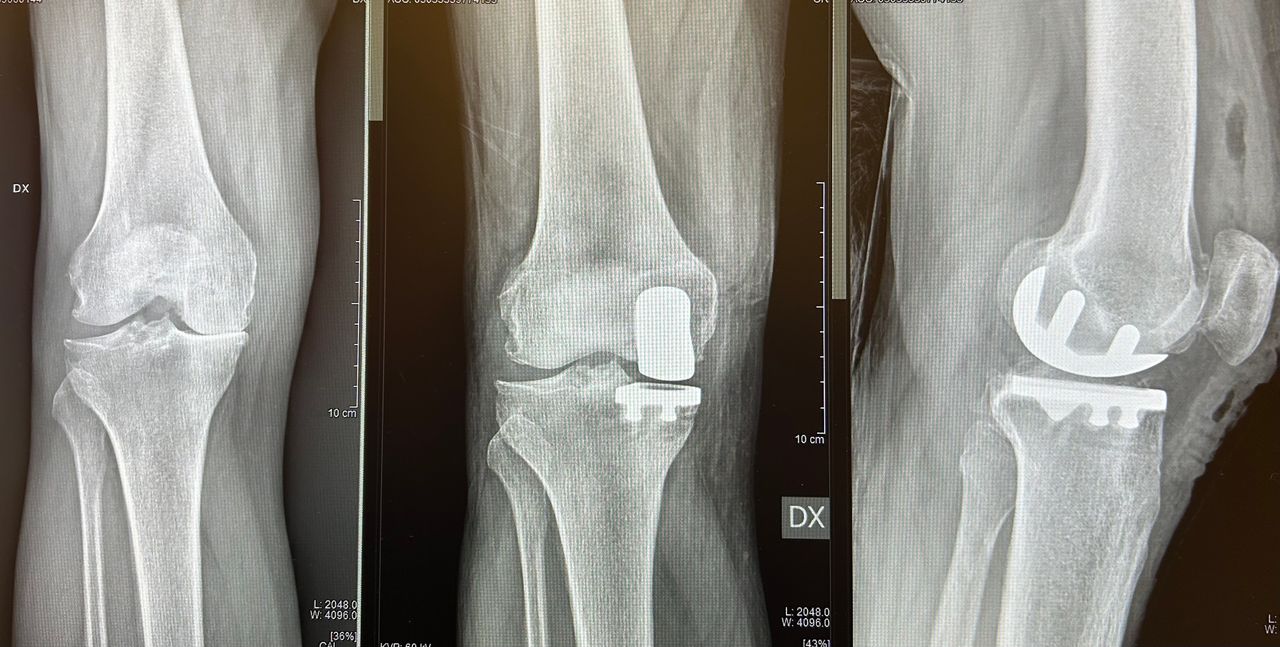

Mi chiamo Luca Luciano e sono un medico ortopedico specializzato nella chirurgia protesica dell’anca e del ginocchio. Da anni mi occupo del trattamento dell’artrosi severa, utilizzando tecniche mini invasive moderne che mi permettono di ridurre il dolore post-operatorio e favorire un recupero più rapido e sereno.

Credo in una chirurgia precisa, attenta e rispettosa dei tessuti. Ogni intervento viene pianificato con cura, valutando la storia clinica, le esigenze e lo stile di vita della persona che ho di fronte. Il mio obiettivo non è solo sostituire un’articolazione consumata, ma restituire qualità di vita, autonomia e sicurezza nei movimenti quotidiani.

• Chirurgia del ginocchio